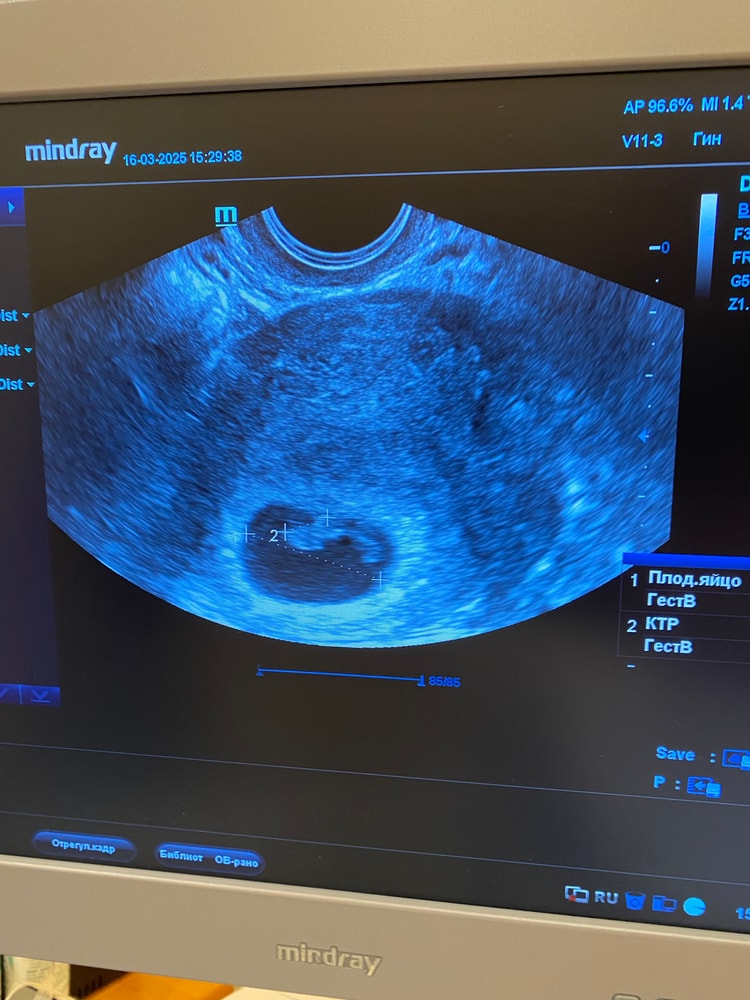

Я пошла на узи в 4.6 увидели плодное яйцо в матке. Ровно через 2 недели уже был эмбрион + сердцебиение. Изображение

Чудо 39, да, это снимок 4 недель 6 дней. А вот снимок 6.6 недель Изображение